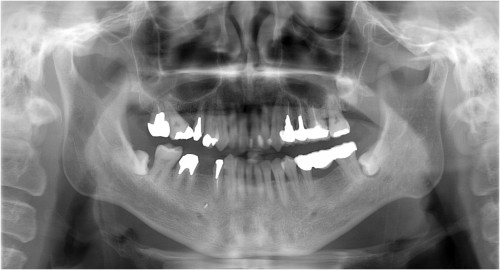

拡大像